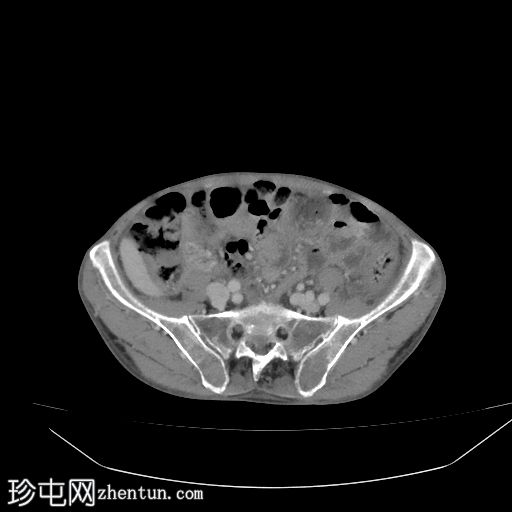

轴位增强扫描

动脉期

盲肠内壁可见多条明显的血管通道,并可见局灶性强化。

动脉期可见一条早期充盈的静脉。静脉期可更清晰地显示扩张的引流静脉。未见活动性出血。